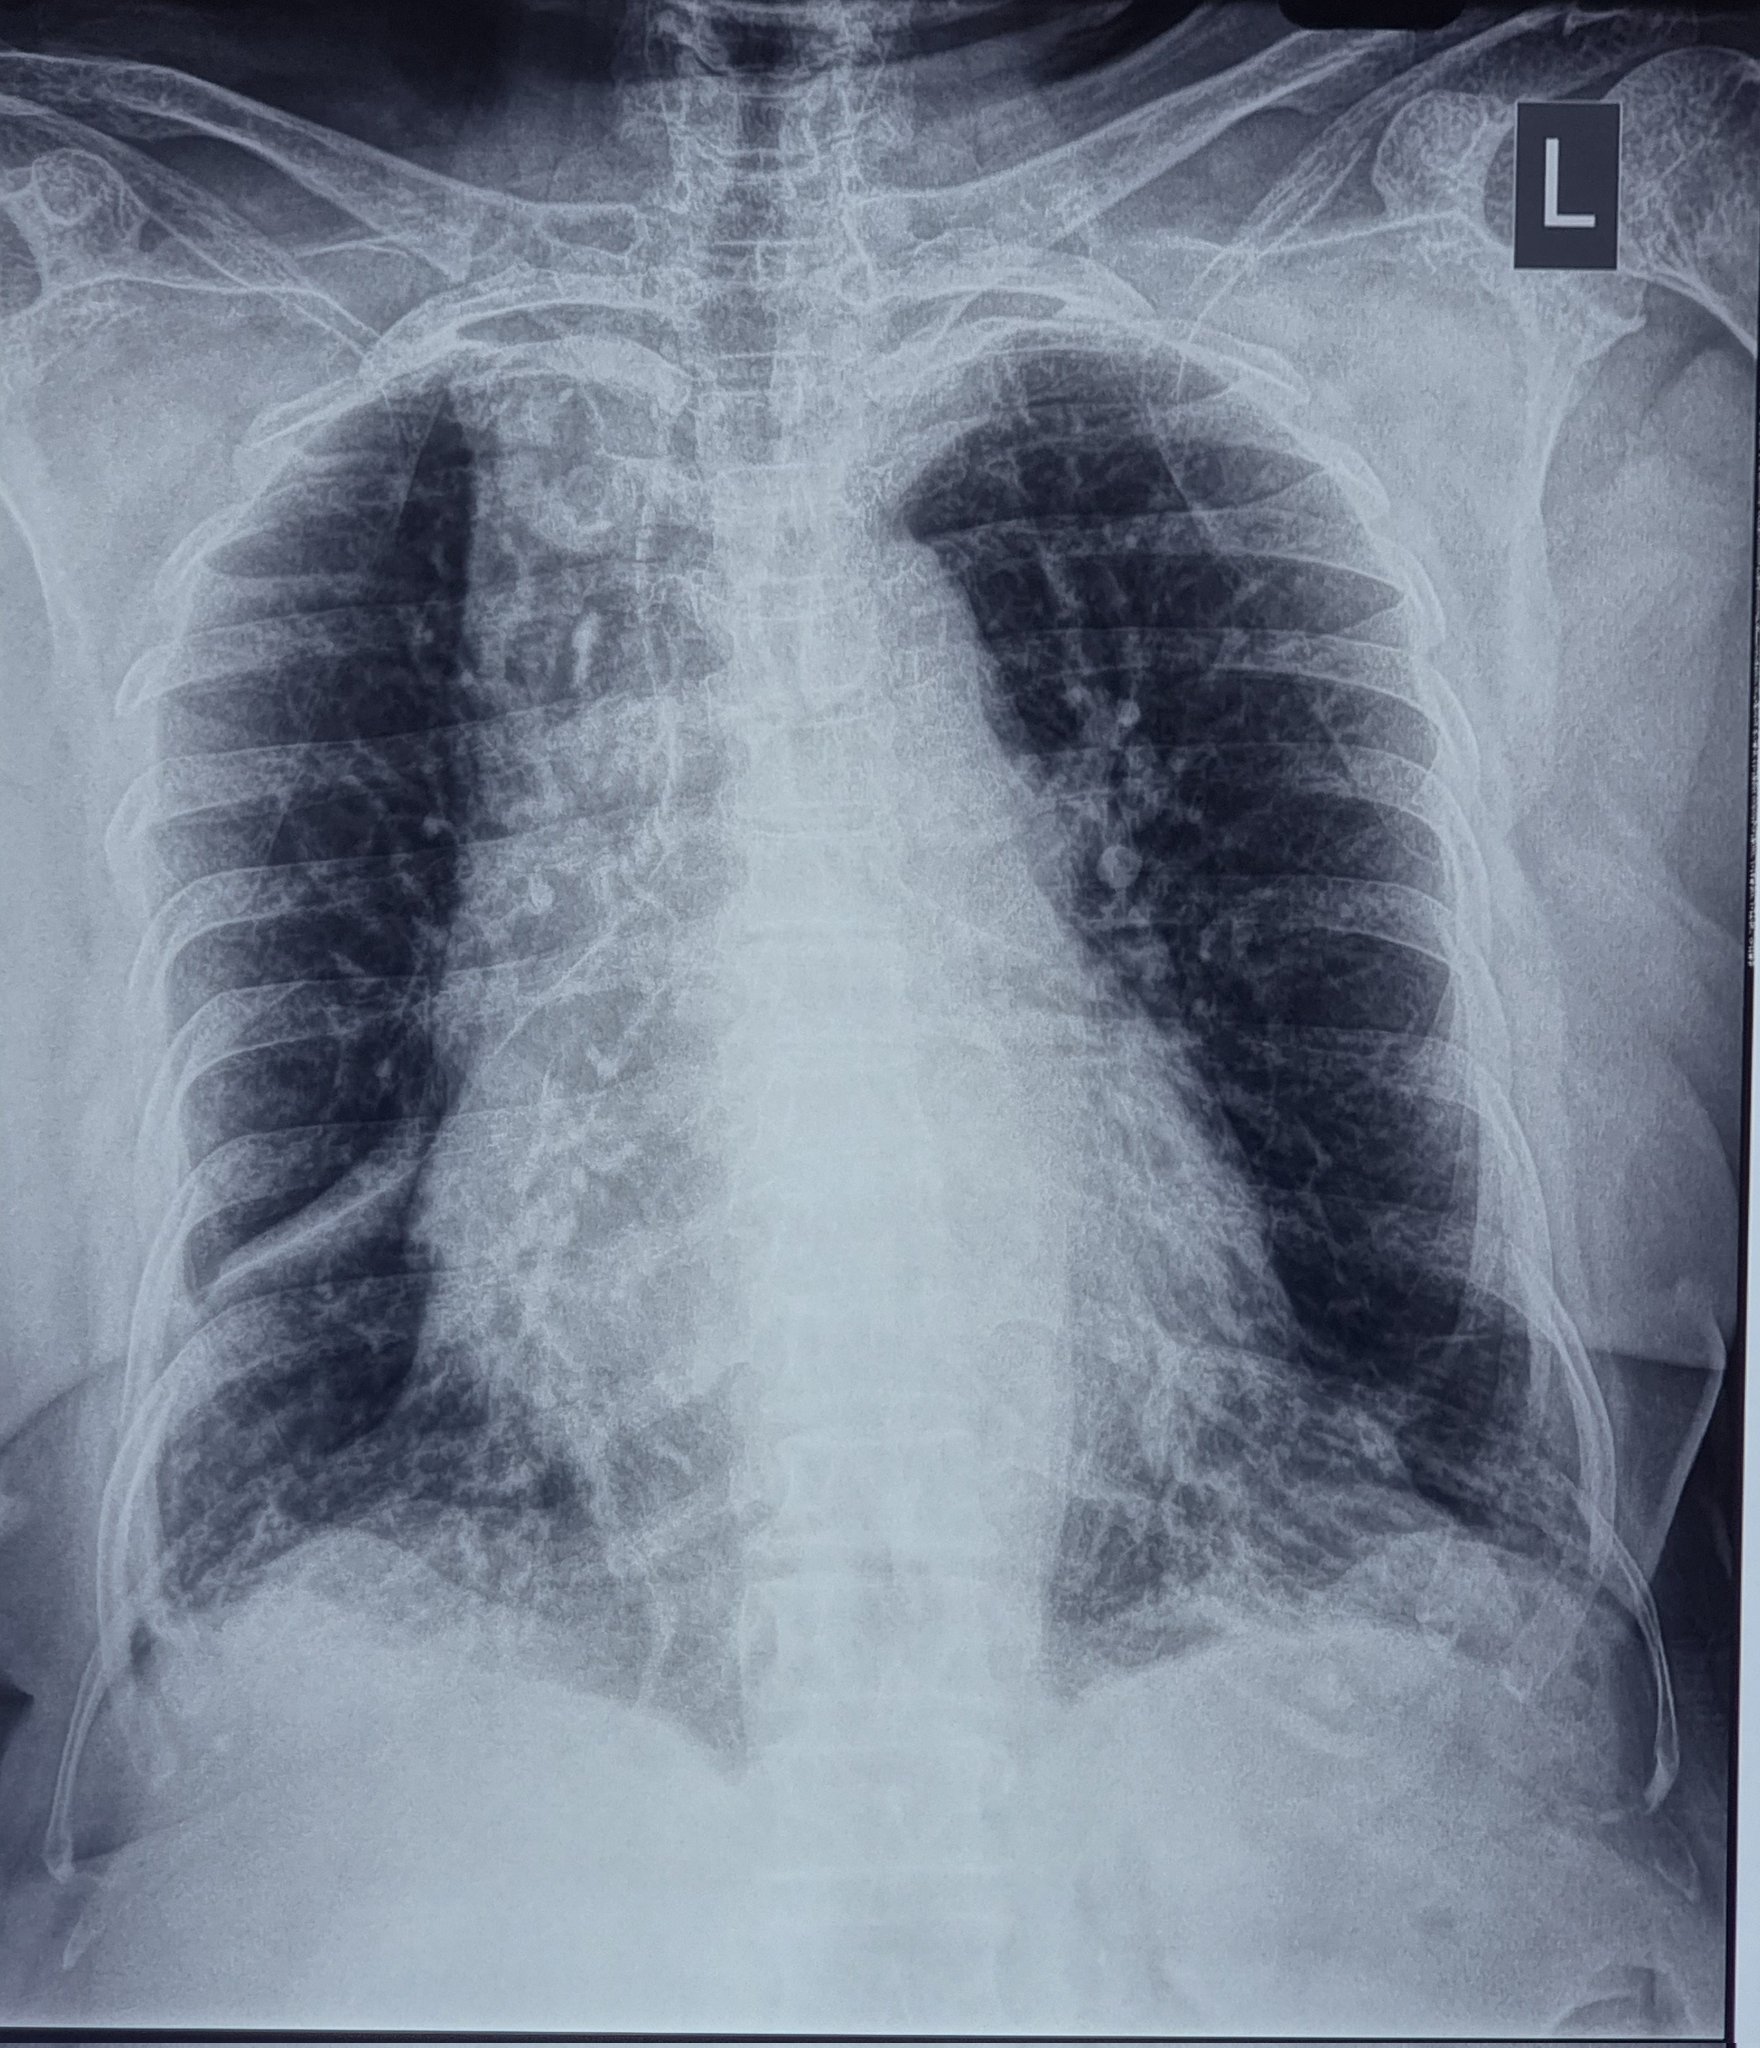

Radiology